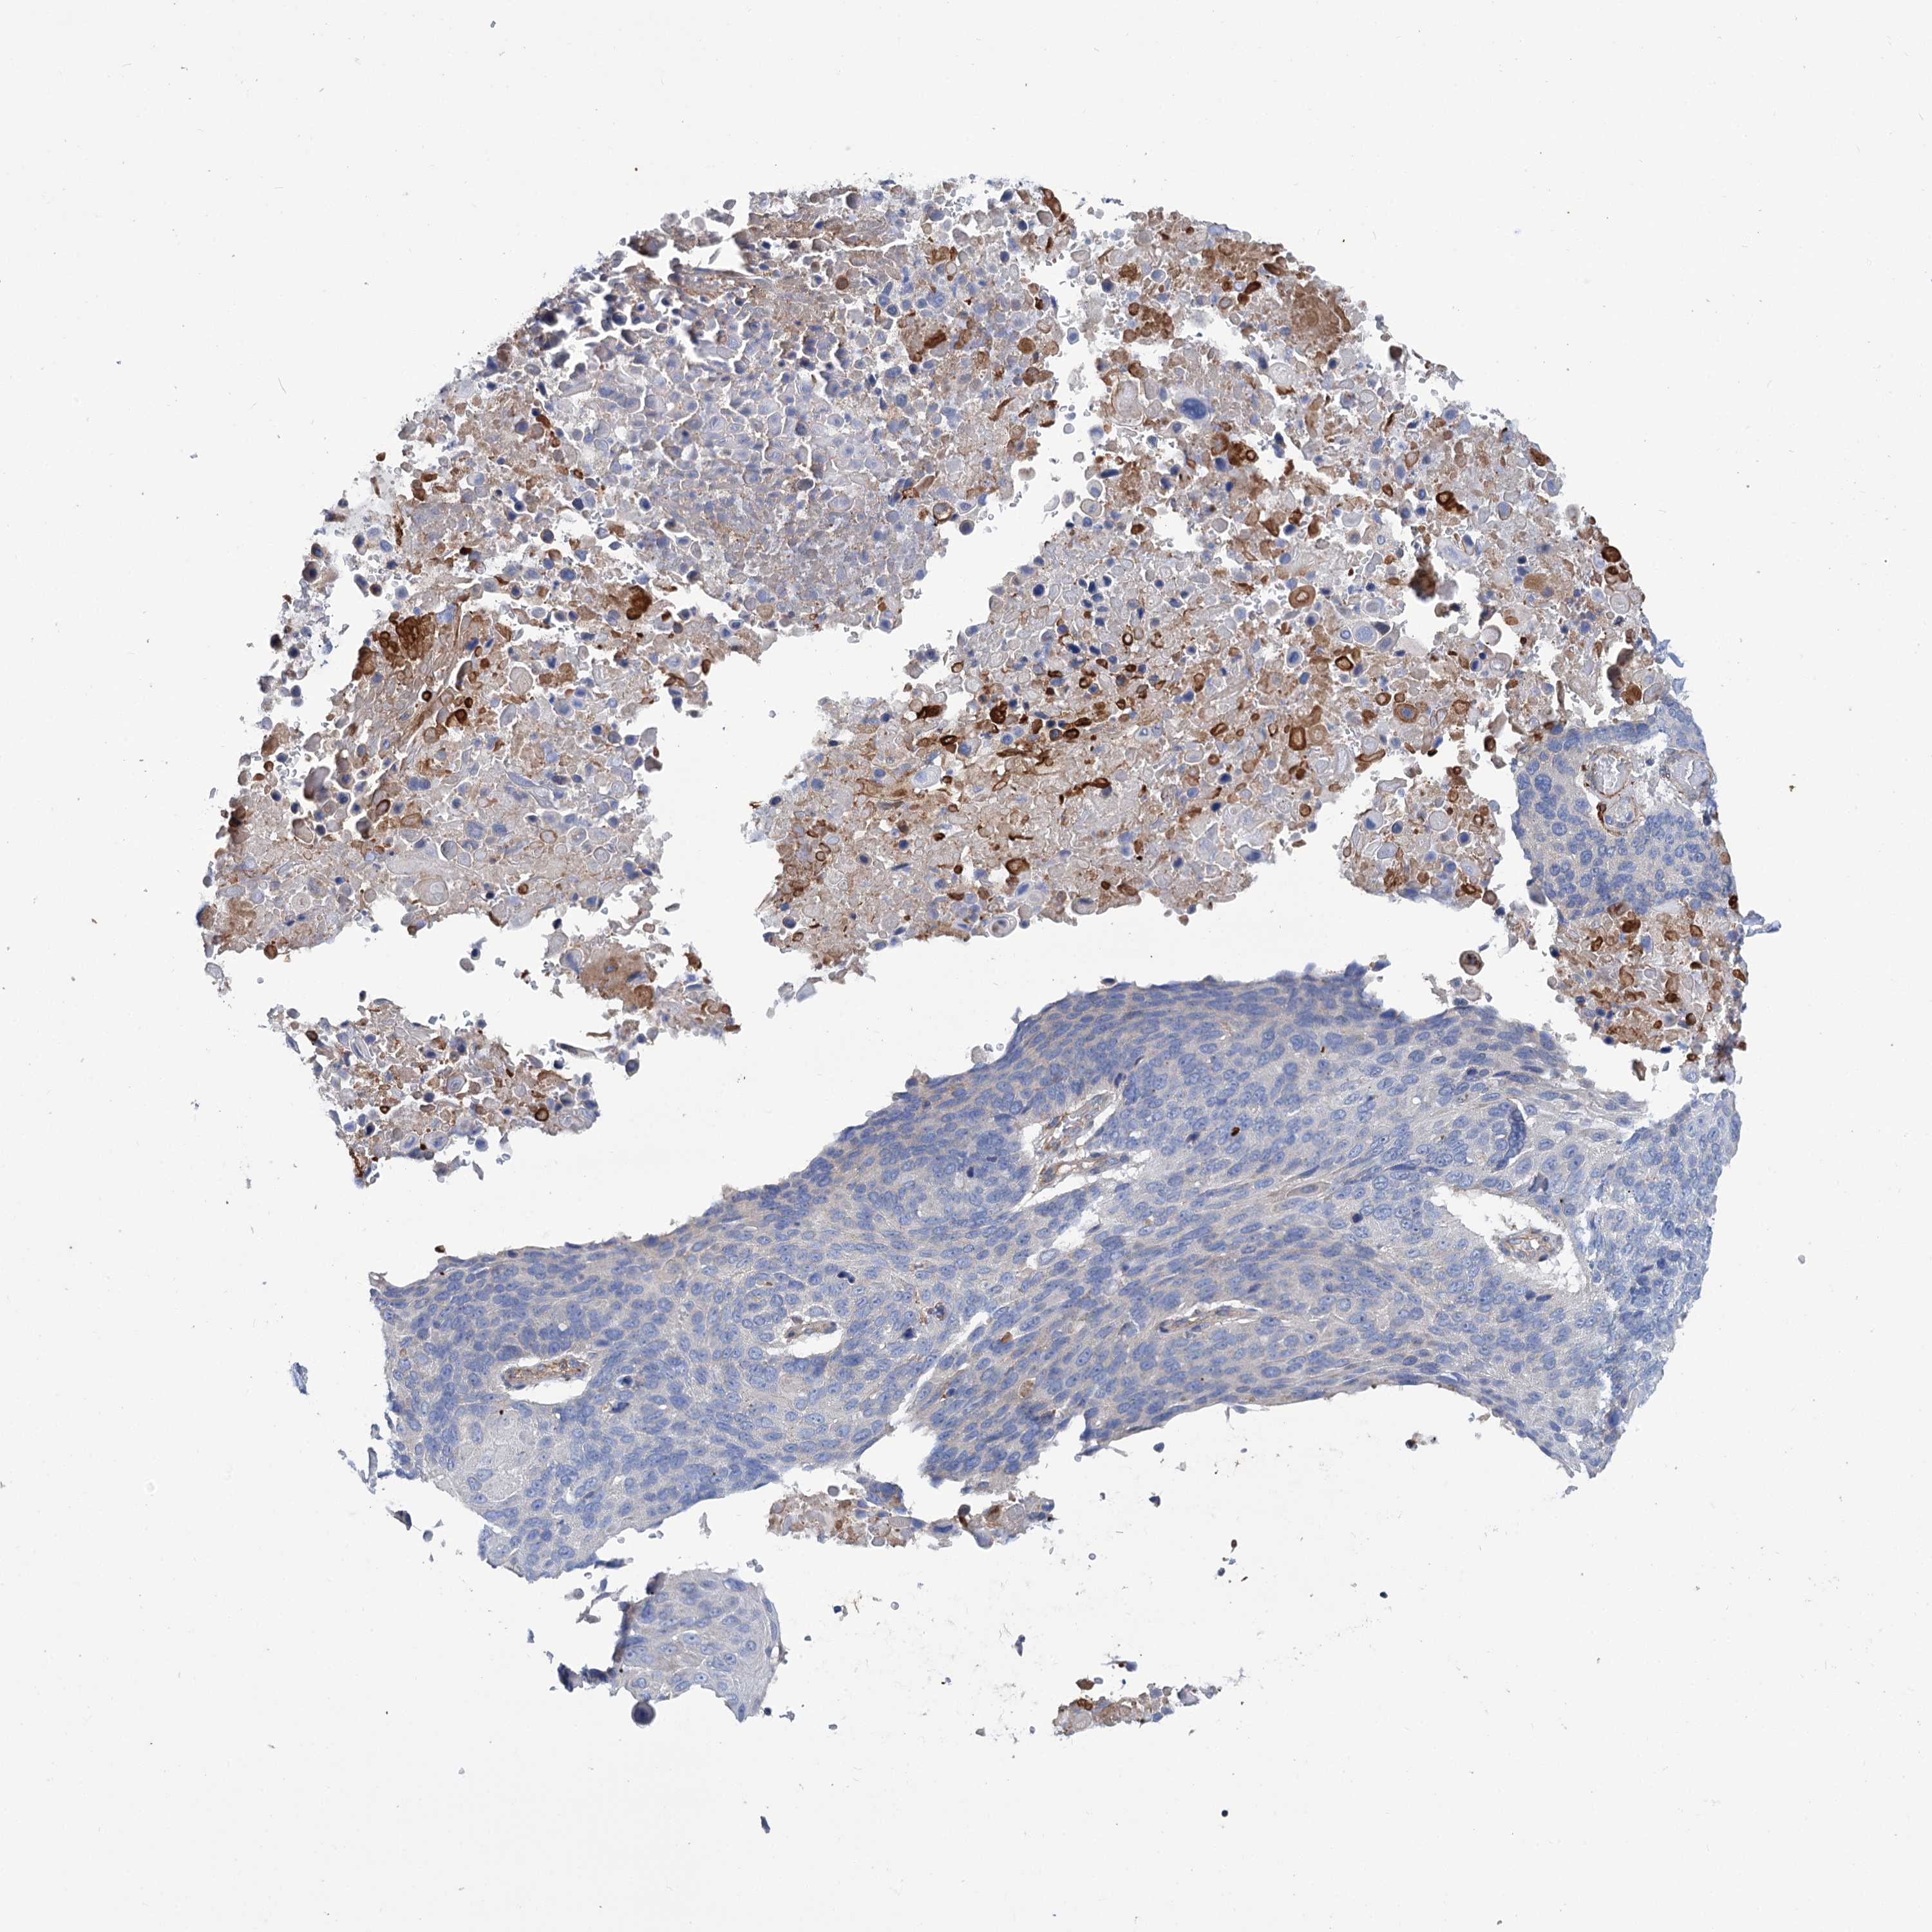

LUNG SQUAMOUS CELL CARCINOMA (TCGA) - Interactive survival scatter ploti

The Survival Scatter plot shows the clinical status (i.e. dead or alive) for all individuals in the patient cohort, based on the same data that underlies the corresponding Kaplan-Meier plots. Patients that are alive at last time for follow-up are shown in blue and patients who have died during the study are shown in red.

The x-axis shows the expression levels (FPKM) of the investigated gene in the tumor tissue at the time of diagnosis. The y-axis shows the follow-up time after diagnosis (years). Both axes are complimented with kernel density curves demonstrating the data density over the axes. The top density plot shows the expression levels (FPKM) distribution among dead (red) and alive patients (blue). The right density plot shows the data density of the survived years of dead patients with high and low expression levels respectively, stratified using the cutoff indicated by the vertical dashed line through the Survival Scatter plot. This cutoff is automatically defined based on the FPKM cutoff that minimizes the p-score. The cutoff can be changed by dragging the vertical line or by entering a cutoff value in the square labeled "Current cut-off".

Under the Survival Scatter plot the p-score landscape (black curve; left axis) is shown together with dead median separation (red curve; right axis). Dead median separation is the difference in median mRNA expression between patients who have died with high and low expression, respectively. It is calculated as follows: median FPKM expression of dead patients with high expression - median FPKM expression of dead patients with low expression. This is intended to aid the user in visually exploring custom cutoffs and the associated p-scores and dead median separation.

Individual patient data is displayed and can be filtered by clicking on one or more of the category buttons on the top of the page. Categories describing expression level and patient information include: high, low, alive, dead, female, male and tumor stages. The scale of the x-axis can be toggled between linear and log-scale by clicking on the "x log" button. Mouse-over function shows TCGA ID, patient information and mRNA expression (FPKM) for each patient.

& Survival analysisi

Kaplan-Meier plots summarize results from analysis of correlation between mRNA expression level and patient survival. Patients were divided based on level of expression into one of the two groups "low" (under cut off) or "high" (over cut off). X-axis shows time for survival (years) and y-axis shows the probability of survival, where 1.0 corresponds to 100 percent.

TRIM55 is not prognostic in Lung Squamous Cell Carcinoma (TCGA)